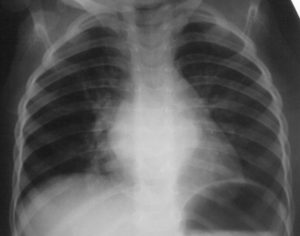

Как выглядит недуг на снимке

После проведения рентгенографии снимки должен изучить специалист, и на основе полученных данных и результатов других исследований сделать соответствующие выводы и поставить диагноз. В норме легкие и бронхи человека выглядят следующим образом:

- легочные доли имеют одинаковый, равномерный черный оттенок;

- в районе сердца наблюдается белый просвет;

- ребра и ключицы серые, с привычными очертаниями;

- купола диафрагмы белого цвета;

- позвоночный столб расположен в центре.

Признаки пневмонии на рентгеновском снимке во многом зависят от формы заболевания и его стадии, а также от локализации патологического процесса. Если исследование показало признаки пневмонии, необходимо как можно скорее приступить к лечению – запущенный патологический процесс опасен не только для здоровья, но и для жизни человека.

Первый признак пневмонии на рентгеновском снимке – появление очагов затемнения с неровными контурами в разных частях легкого, которые могут иметь разный размер, от 3-4-х до 12 мм.

Тени различают по внешнему виду (круглые, овальные кольцевидные) и интенсивности окраски – чем темнее пятно, тем сильнее выражен патологический процесс.

При поражении лимфатических узлов и нарушении кровоснабжения органа могут наблюдаться изменения корней легких, а если болезнь затронула плевру – нарушение в рисунке куполов диафрагмы. В остальном проявления пневмонии зависят от стадии, формы и клинических особенностей заболевания:

- Очаговая форма. На рентгене отображаются небольшие (1-1,5 см) тени со слабой или умеренной интенсивностью окраски, неоднородной структурой и нечеткими границами. Очаги поражения могут быть единичными или множественными, а в некоторых случаях они сливаются в одно большое пятно. Корни легких расширены, причем нарушения нормального рисунка органа могут сохраняться в течение нескольких дней после выздоровления.

- Крупозная пневмония. Наблюдаются изменения нормального легочного рисунка, жидкость в полости плевры, признаки инфильтрации одной из долей легкого, расширение корней. По мере развития воспалительного процесса выраженность изменений и интенсивность окраски затемнений усиливается.

- Интерстициальная форма. На снимке заметно уплотнение корней легких и другие изменения, которые формируют выраженный рисунок, напоминающий ветви дерева.

- Абсцедирующая пневмония. Проявляется обширным затемнением пораженной области, признаками утолщения плевры и наличием полостей разного размера, наполненных жидкостью.

- Аспирационная форма. Рентген характеризуется треугольными пятнами с однородной структурой, светлыми очагами и приподнятой диафрагмой.